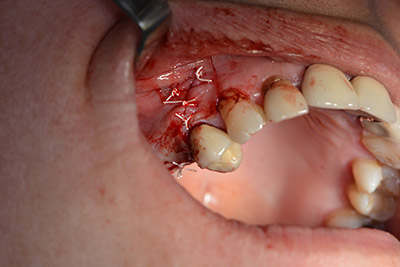

Използвана е абсорбираща мембрана като бариера на букалната страна и покритие на аугментацията. Накрая са поставени устойчиви на слюнка конци (Фиг. 15 до 19).